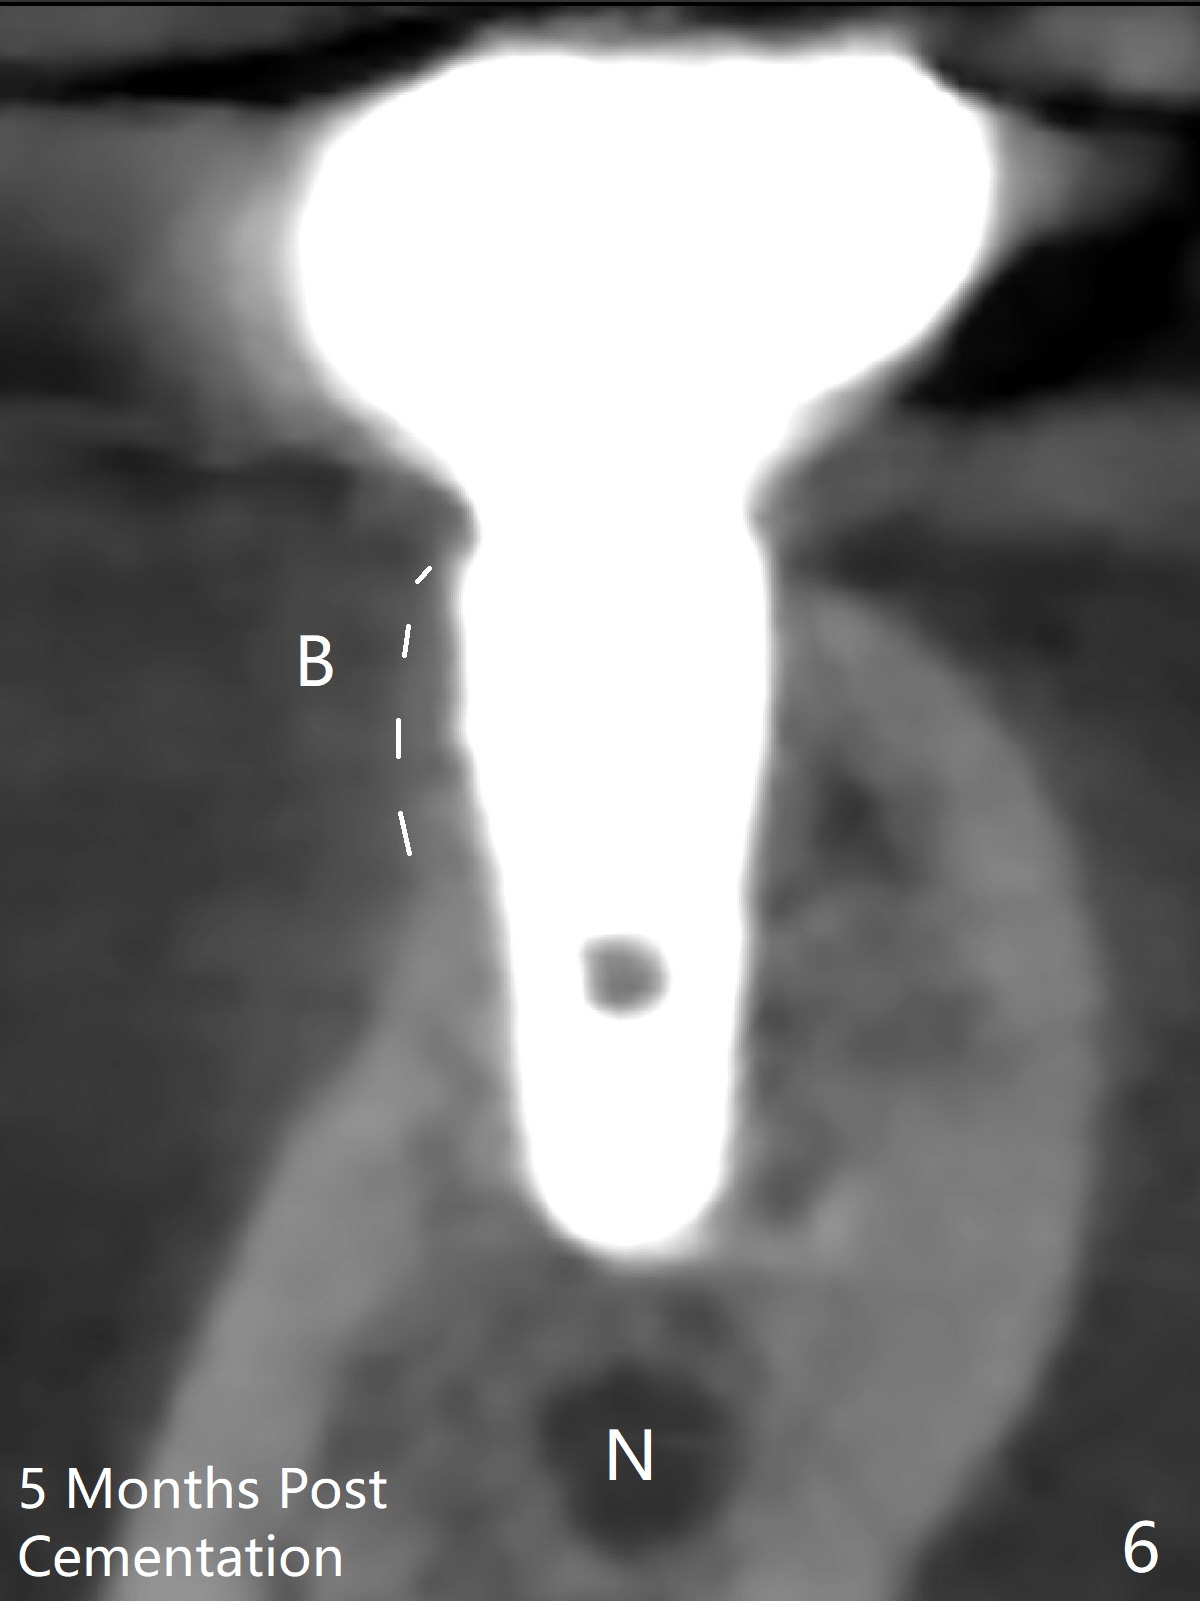

The ridge at #30 is not so narrow (Fig.1). Initial depth is 10 mm with 2 mm from the Inferior Alveolar Canal (Fig.2,3 red dashed line). A 4.5x10 mm implant is placed with > 50 Ncm; a 6.2x5(3) mm healing abutment placed (Fig.4). The implant is stable and seems to be ready for impression 3 months postop (Fig.5). CT taken 5 months post cementation shows that the implant could be placed more lingually (Fig.6 (coronal section; B: buccal)). Periradicular radiolucency at #31 (Fig.7 *) is continuous with the Inferior Alveolar neurovascular bundle (N). After extraction, care should be taken to remove granulation tissue. The tooth #32 will be extracted simultaneously because of severe bone loss.